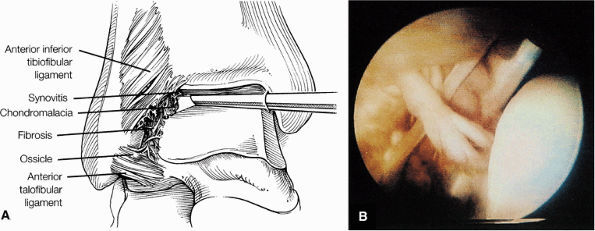

Medial osteochondral talar dome lesion. There is a fragment of osseous tissue within the osteochondral bed that may be attached by synovium. The fragment measures 8 mm anterior to posterior and 3 mm medial to lateral. This correlates with a stage III osteochondral lesion. There is associated bone marrow edema of 10 mm and subchondral sclerosis. There is irregularity of the overlying subchondral plate. There are also mild cystic changes in the adjacent portion of the talus, although no fluid is directly undermining the osteochondral lesion itself.

Anterior osseous impingement of the ankle with spurring of the anterior aspect of the tibiotalar joint and bone marrow edema demonstrated in the anterior distal tibia

Chronic thickening of the anterior talofibular ligament without disruption